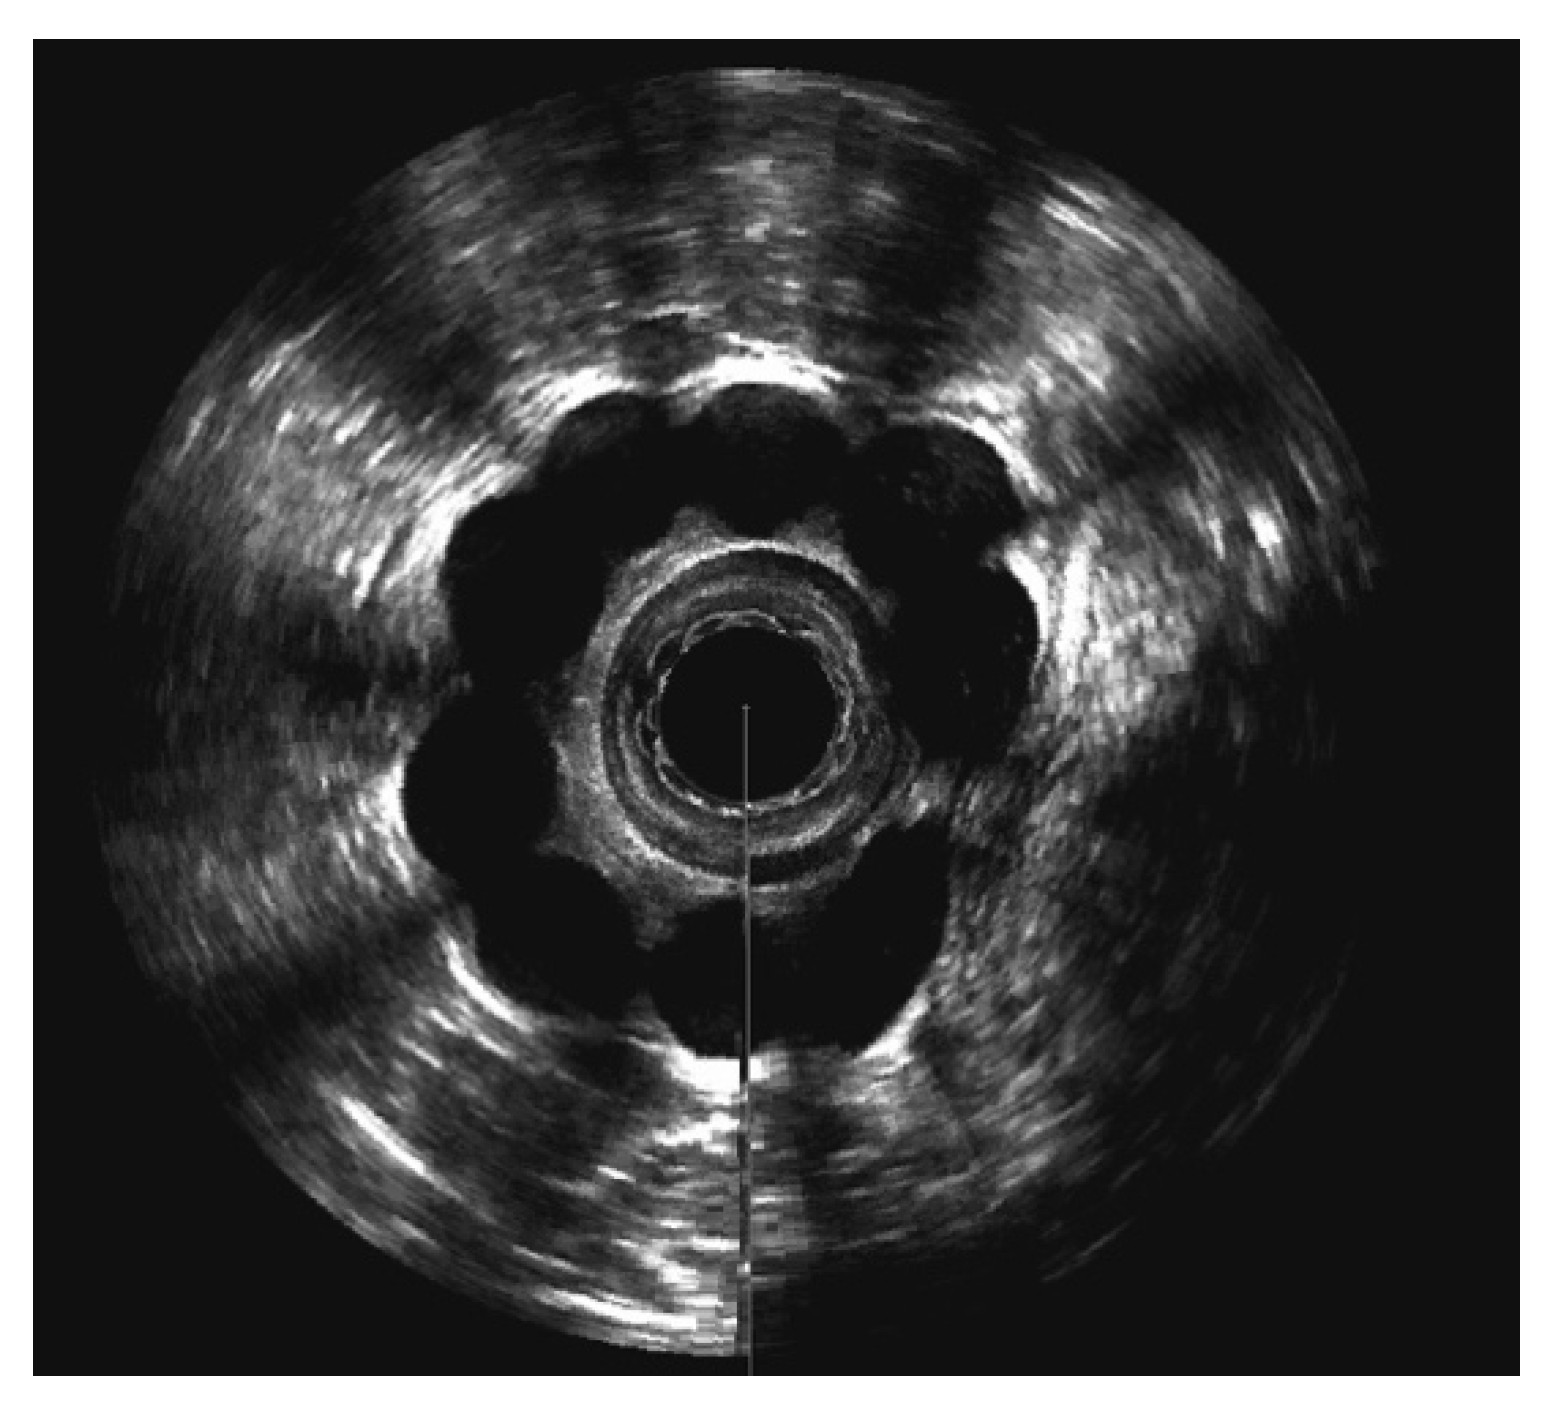

3.4. Evaluation of Sphinkeeper Implants

| EAUS—internal sphincter defect [grade], median (range) | 67.5 (38–121) |